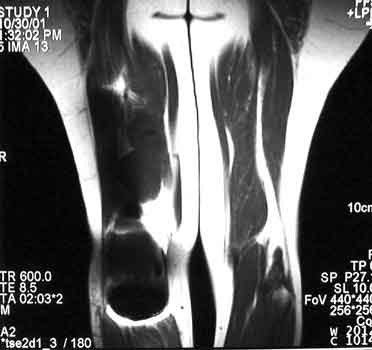

Recurrent osteosarcoma in patient status post resection of femur and placement of modular endoprosthesis. Axial T1 and STIR sequences clearly demonstrate mass adjacent to endoprosthesis.